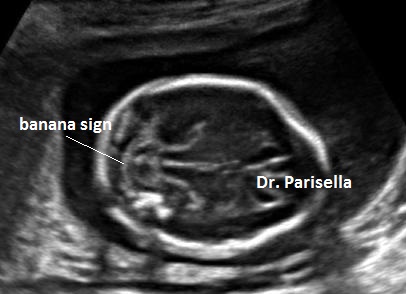

Macrocefalia/Macrocrania è presente nella Acondroplasia, nella Displasia Tanatofora ( il tipo II è caratterizzato da “cranio a trifoglio” ), nell'Acondrogenesi. L'idrocefalia può essere una complicazione dell'Acondroplasia, dell'Osteogenesi Imperfetta e della Displasia Metatropica. Un cranio di consistenza molle (ossa wormiane) è sintomo costante di Osteogenesi Imperfetta anche se può essere presente in altre condizioni quali l'ipofosfatasia, la displasia cleido-cranica, etc. Nell'Ipofosfatasia vi può essere una aumentata ecogenicità della falce cerebrale.